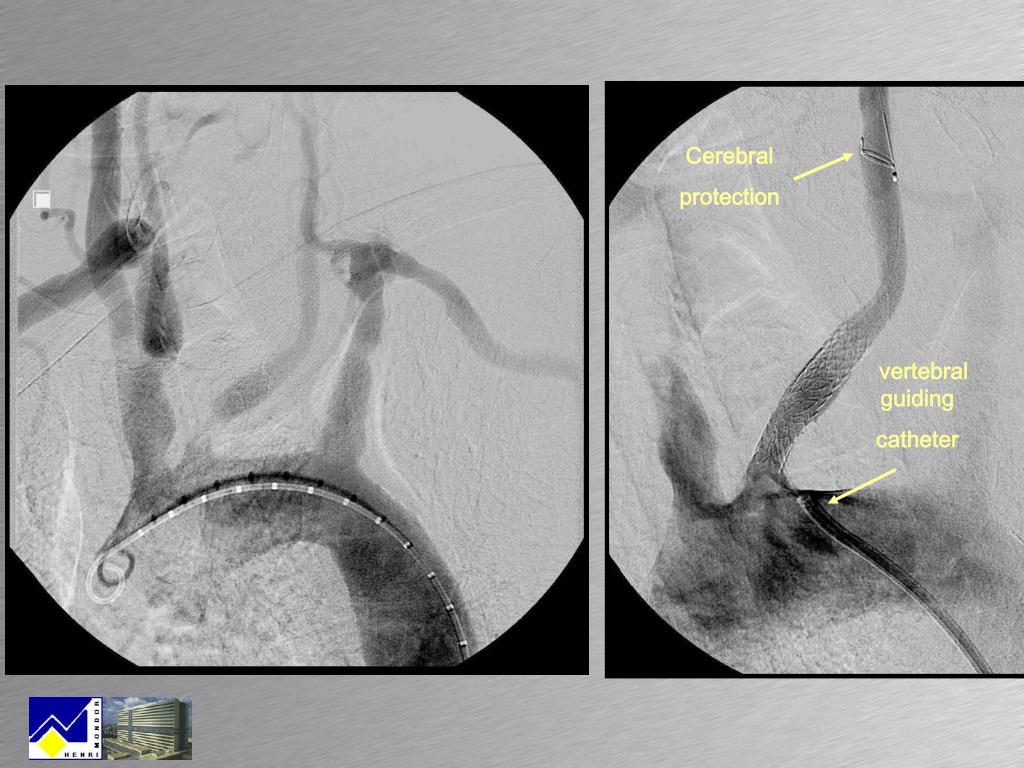

30. Cerebral protection vertebral guiding catheter